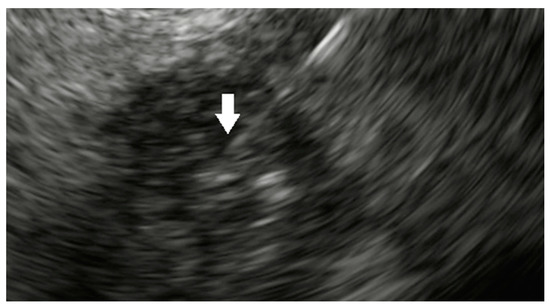

- Sun, S.; Xu, H.; Xin, J.; Liu, J.; Guo, Q.; Li, S. Endoscopic Ultrasound-Guided Interstitial Brachytherapy of Unresectable Pancreatic Cancer: Results of a Pilot Trial. Endoscopy 2006, 38, 399–403. [Google Scholar] [CrossRef] [PubMed]

- Jin, Z.; Du, Y.; Li, Z.; Jiang, Y.; Chen, J.; Liu, Y. Endoscopic ultrasonography-guided interstitial implantation of iodine 125-seeds combined with chemotherapy in the treatment of unresectable pancreatic carcinoma: A prospective pilot study. Endoscopy 2008, 40, 314–320. [Google Scholar] [CrossRef]

- Bhutani, M.S.; Klapman, J.B.; Tuli, R.; El-Haddad, G.; Hoffe, S.; Wong, F.C.L.; Chasen, B.; Fogelman, D.R.; Lo, S.K.; Nissen, N.N.; et al. An open-label, single-arm pilot study of EUS-guided brachytherapy with phosphorus-32 microparticles in combination with gemcitabine +/- nab-paclitaxel in unresectable locally advanced pancreatic cancer (OncoPaC-1): Technical details and study protocol. Endosc Ultrasound. 2020, 9, 24–30. [Google Scholar] [CrossRef]

- Ross, P.J.; Meenan, J.; O’Doherty, M.; Palmer, D.; Heatley, S.; Calara, J.; Chow, P. Novel delivery via endoscopic ultrasound of a 32P brachytherapy device in addition to gemcitabine (G) in advanced pancreatic cancer. ASCO 2008. [Google Scholar]